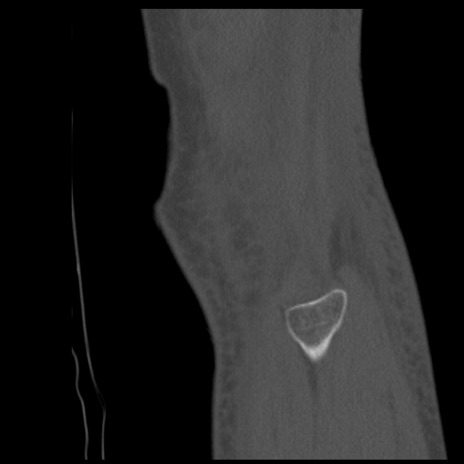

症例28 右膝関節CT(矢状断像)

右膝関節CT